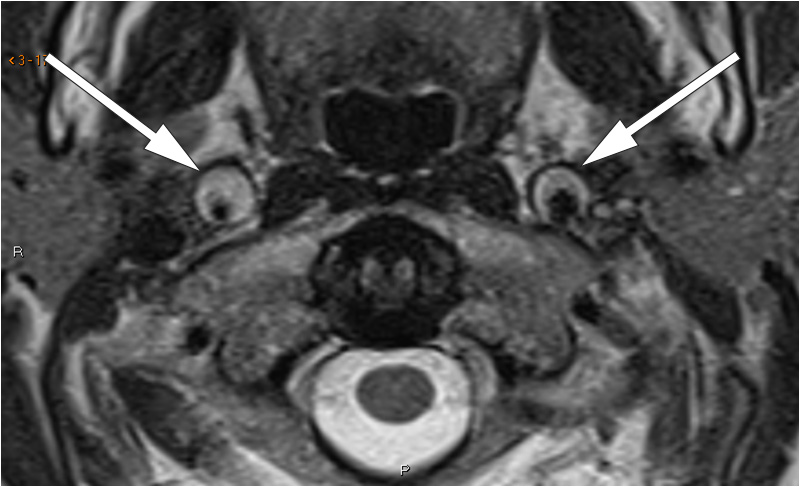

The neurological workup revealed Horner’s syndrome. CT angiography showed thickening of the walls of both internal carotid arteries, most pronounced on the right, from just above the bifurcation to the base of the skull. MR angiography and T2-weighted images confirmed bilateral carotid artery dissection, with a minimal lumen diameter of 2 mm on the right side (images to left and centre). Fat-suppressed T1-weighted images (right) showed high signal intensity in the arterial walls, consistent with intramural haematomas.